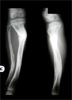

Intra

Op

Acute shortening held with wires